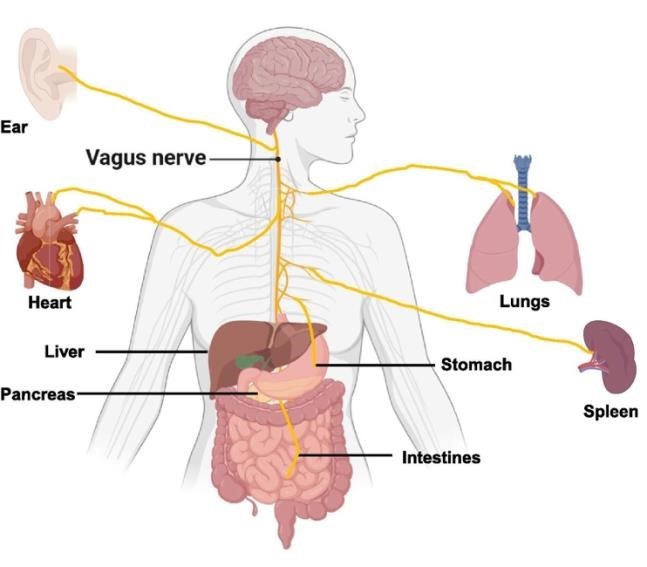

- Kriittinen katsaus vagushermoonkirjoittanut Eetu Koivisto